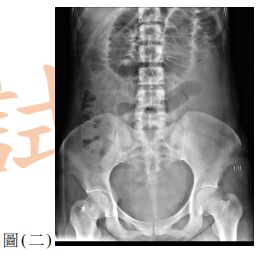

12. 一位 25歲男性因呼吸困難至急診就醫,主訴2天前工作撞擊到右側胸部,胸部X光檢查如圖(三),下列處置何者較適當?

(A) 立即給予右側胸管置入引流(B) 觀察呼吸困難狀況並給予肌肉鬆弛劑(C) 立即安排胸腔鏡手術治療(D) 安排胸部電腦斷層檢查確立診斷